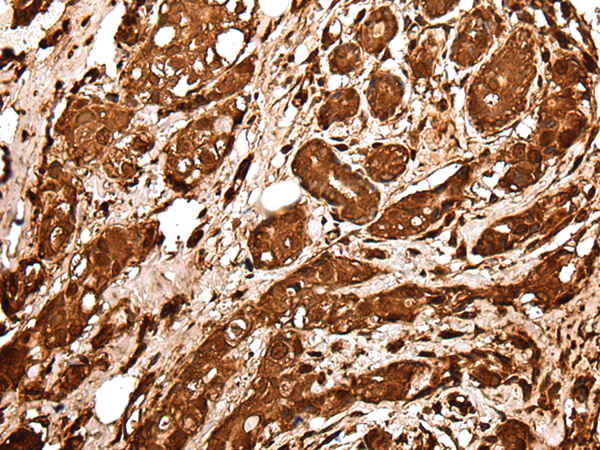

IHC positive control: |

Human prostate cancer and human tonsil |

IHC Recommend dilution: |

25-100 |